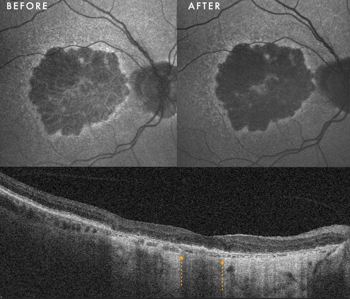

Clinical presentation: A 76-year-old man presented with late-stage atrophy. He had previously sought multiple opinions and had even considered travelling overseas for Valeda treatment. OCT imaging revealed a precarious foveal island in the form of preserved outer nuclear layer (ONL) surrounded by dense atrophy.

Case 3, Fig 3. Fundus autofluroescence shows a faint hyperautofluorescent signal at the fovea before PBM, which has increased significantly after PBM. The OCT demonstrates the foveal island of outer nuclear layer (between the yellow arrows) surrounded by hyper transmission/atrophy on either side. BCVA improved from 6/24 to 6/18

Response to therapy: Contrary to the poor prognosis usually associated with this phenotype, the patient achieved a 1-line improvement in BCVA (improving from 6/24 to 6/18 in the worse eye). Anatomically, we observed an increase in the hyperautofluorescent signal within the central island of residual RPE. This finding could suggest revitalisation of metabolically active tissue and potential reversal of nascent atrophic wipeout at the fovea.

Clinical implication: This case challenges the therapeutic nihilism often applied to advanced dry AMD. It suggests that as long as islands of foveal ONL persist on OCT, the tissue may remain responsive to metabolic support. PBM could potentially extend the window of useful central vision, even in the face of severe structural loss.